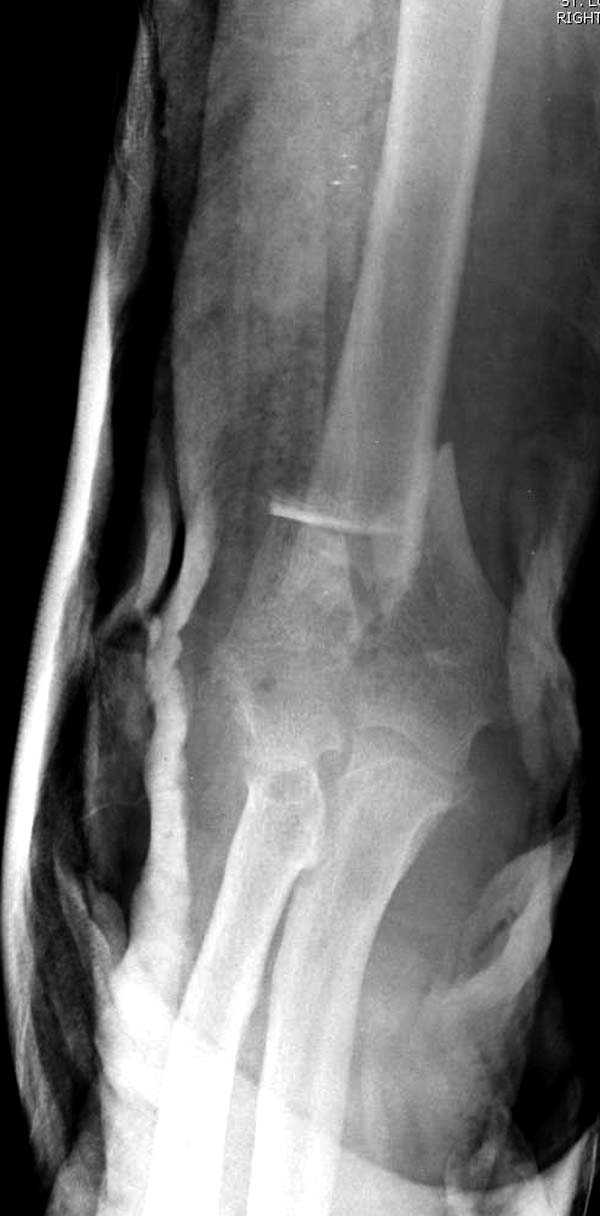

Примеры: первому более 15 лет фиксирован шурупом и tension band

technique, а второй перелом открытый больной 80 лет, после наружного

фиксатора в первом этапе и окончательная фиксация вторично. Третьий раз

внесуставная остеотомия...

Имя     : 3-1 Humerus prox distal.jpg

Тип     : image/jpeg

Размер  : 41125 байтов

Описание: отсутствует

Url     : http://weborto.net:8080/pipermail/ortho/attachments/20130604/c45a379f/attachment-0027.jpg